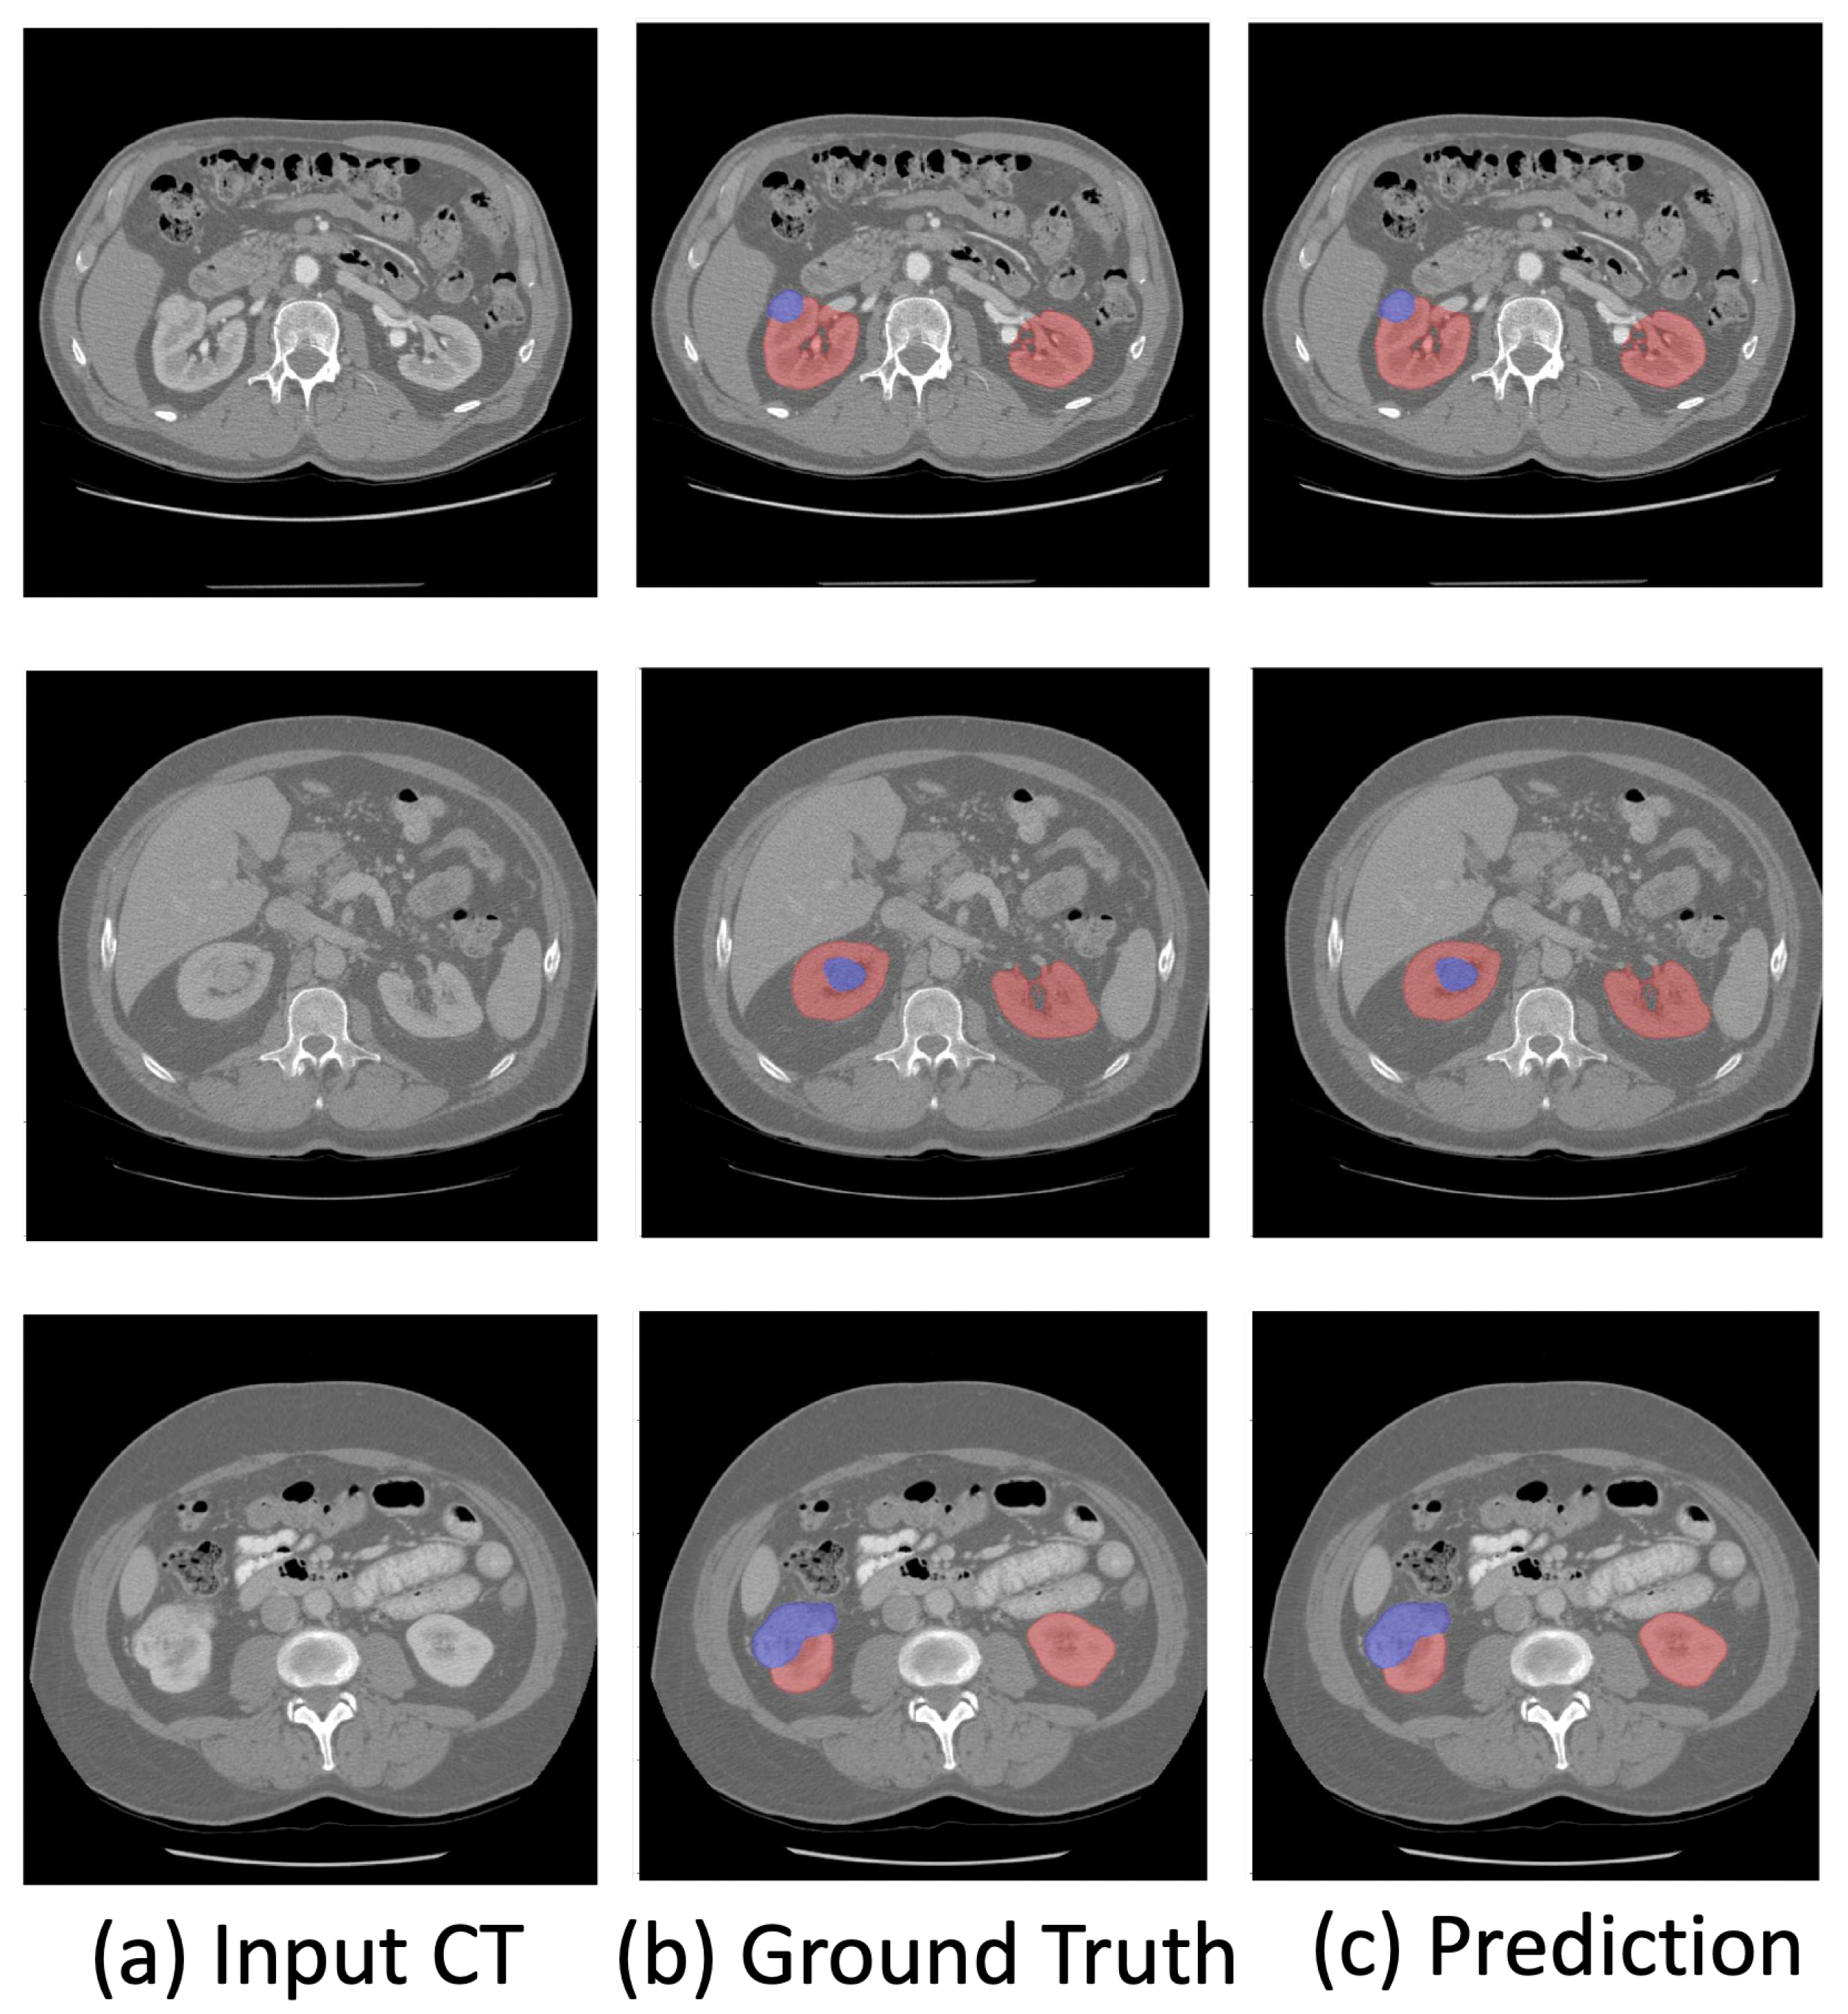

- We propose a novel kidney and renal mass diagnosis framework integrating 3D segmentation and renal mass subtype classification. It provides an easy-to-analyze 3D morphologic representation of the kidney and renal mass with the subtypes. The segmentation method adopts the basic 3D U-Net structure with residual blocks included for gaining the cross-layer connections. The postprocessing steps further improved the accuracy and reduced false positives by small region detection. The classification network applies the dual-path schema to combine the different fields of view for the prediction of subtypes.

- The experimental results on the KiTs19 dataset demonstrate the state-of-the-art performance on kidney and renal mass segmentation and classification. Additionally, the results on three NIH datasets (the TCGA-KICH [15], TCGA-KIRP [16], and TCGA-KIRC [17] datasets) show that the proposed framework can be robust in different institutions with few annotations.

4.4.1. Comparison with the State-of-the-Art Methods